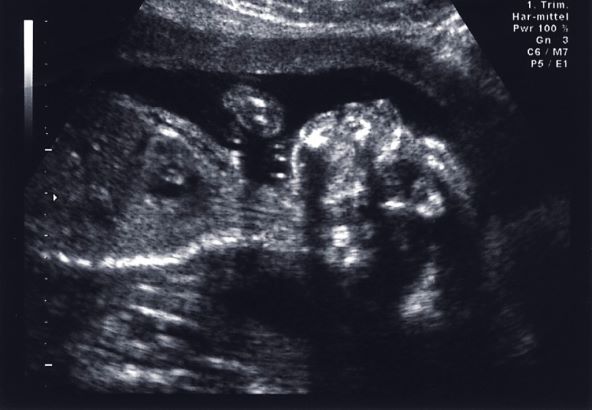

U četvrtak, 7. prosinca došla sam na redovni CTG, kada su bebi registrirani otkucaji srca, ali se smirilo pa mi je rečeno da se vratim za dva sata (u međuvremenu da prošetam). Na ponovljenom CTG-u sve je bilo u redu pa sam za dva dana zakazan drugi pregled, u subotu 9.12. Već tada mi je CTG bio normalan, a ultrazvučni pregled je opet pokazao višak plodne vode. Zbog toga mi je doktor zakazao pregled za utorak, da vide zašto se višak ponovno pojavio.